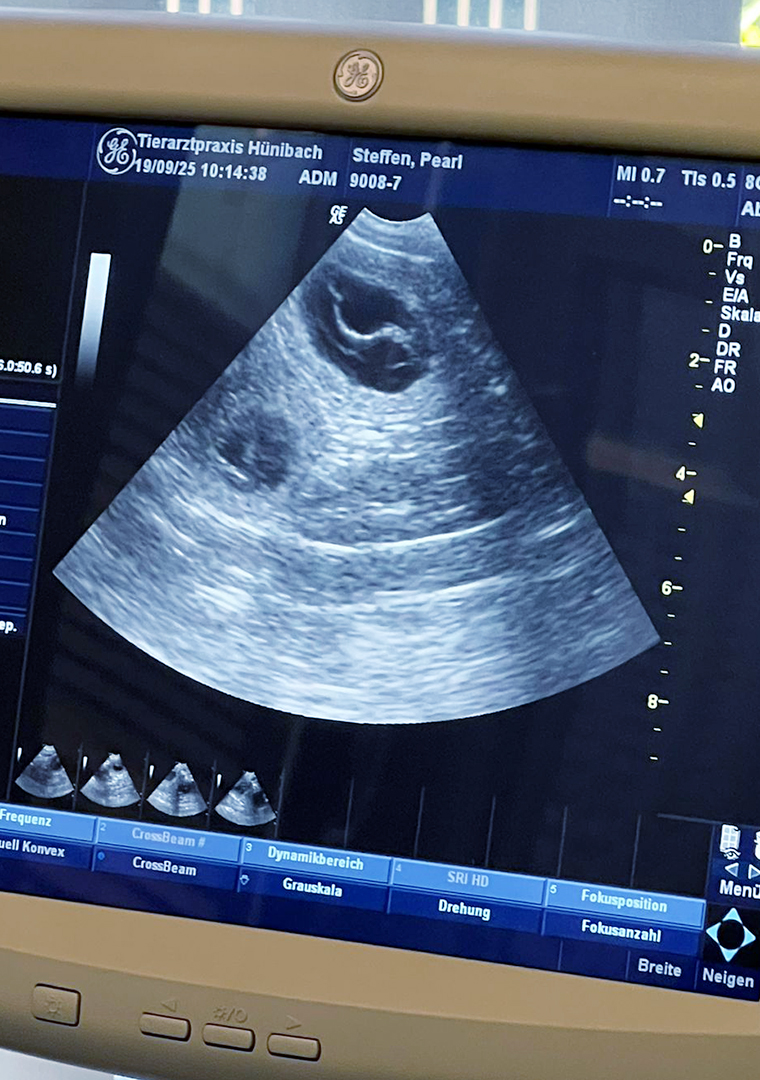

Wir sind sehr happy! Pearl und Barclay werden Eltern – das hat die Ultraschall-Untersuchung bei Dr. med. vet. Daniel Zimmerli gezeigt. Wir sind sehr dankbar und freuen und auf unseren V-Wurf!

Mehr über die Verpaarung siehe V-Wurf von Pearl